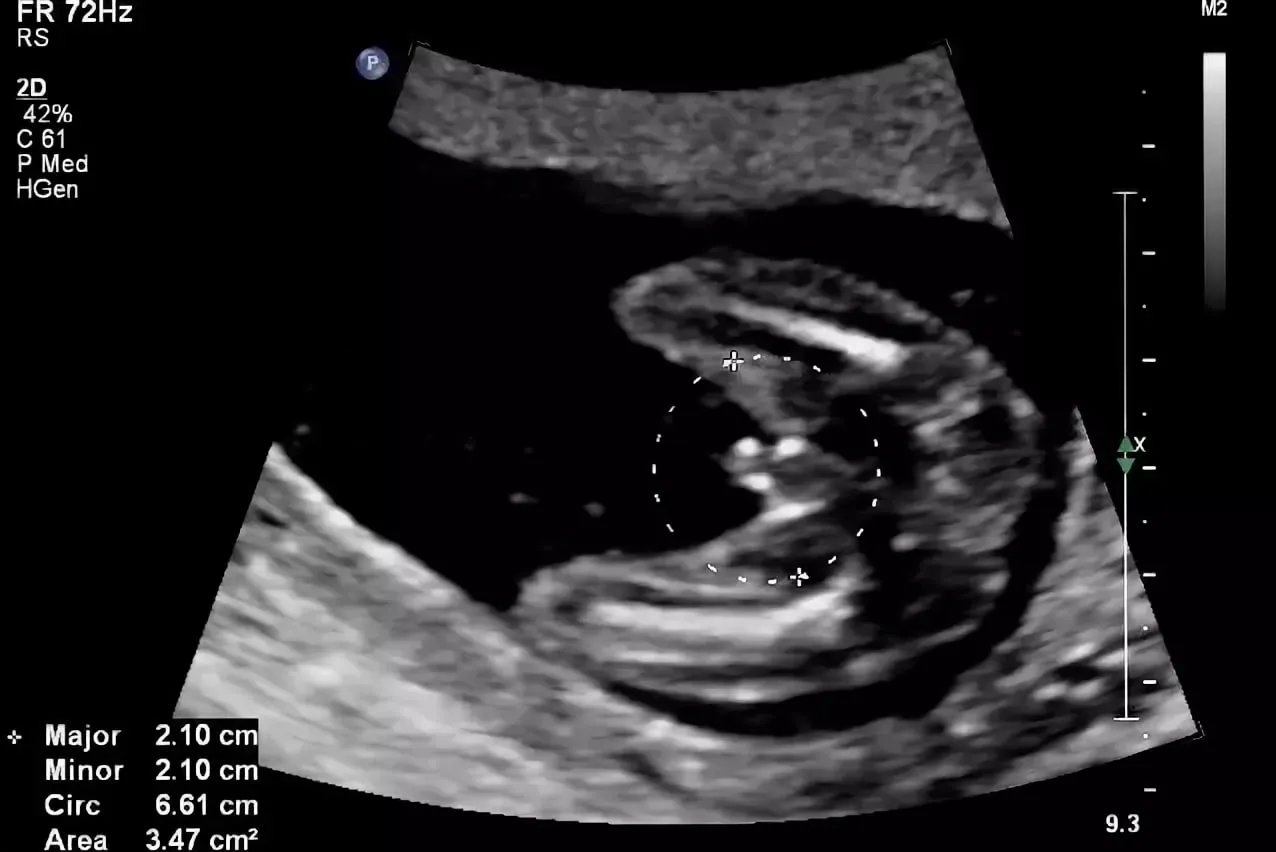

Пол на 14 неделе беременности по узи

Пол на 14 неделе беременности по узи 88 фото